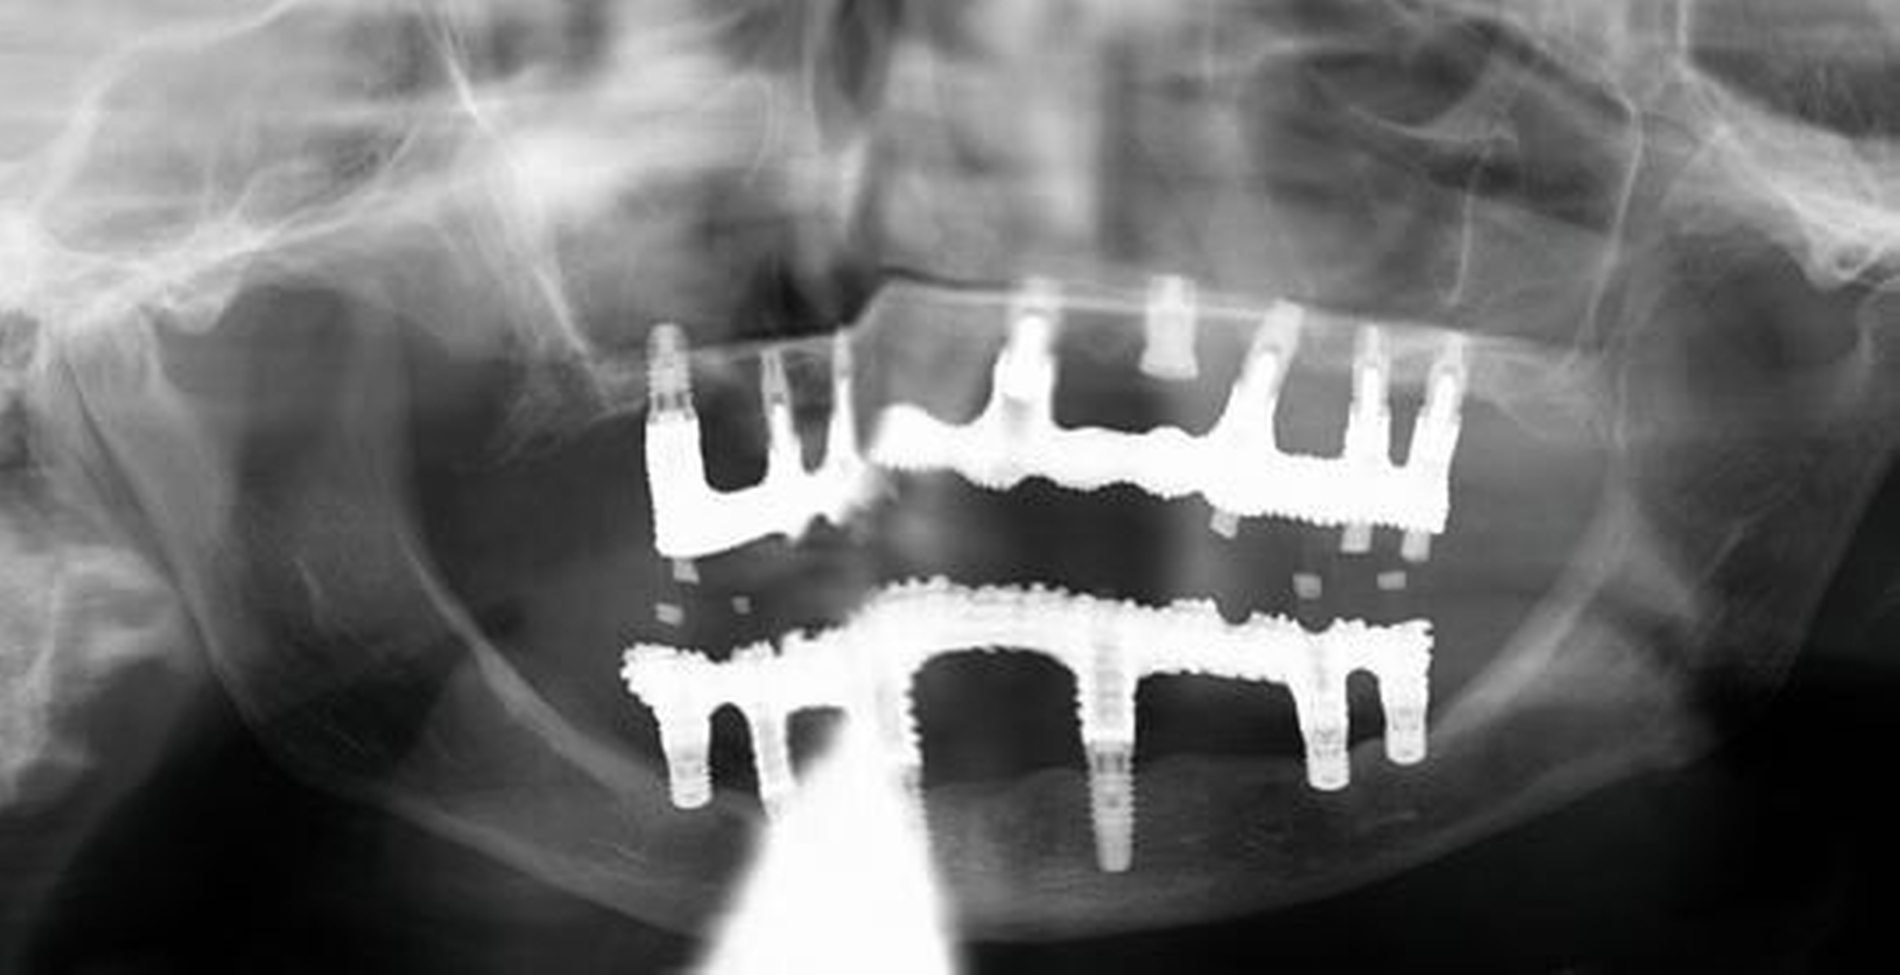

Die längere Lebenserwartung und mehr eigene Zähne sind für das Gesundheitssystem eine große Herausforderung. Bei Zahnlosigkeit ist die klassische Totalprothese das Mittel der Wahl, was eine kosteneffiziente Lösung bedeutet, im individuellen Fall aber mit einer erheblichen Beeinträchtigung der Lebensqualität durch eine eingeschränkte Kaufunktion, eine eingeschränkte Phonetik und psychosozialen Einfluss verbunden sein kann. Mehr eigene Zähne oder Implantate bedeuten mehr Lebensqualität, bedingen aber einen höheren Nachsorge- und Mundhygieneaufwand, höhere Kosten bei prothetischen Versorgungen und ein gewisses Risiko für die Zukunft. Müssen Zähne oder Implantate nämlich entfernt werden und hat sich die allgemeine Gesundheitssituation erheblich verschlechtert, kann dies in einigen Fällen nur unter Vollnarkose durchgeführt werden, was weitere gesundheitliche Risiken (zum Beispiel Delir) mit sich bringt. Auch die Überführung einer festsitzenden prothetischen Restauration in eine abnehmbare kann die Adaptationsfähigkeit im Alter übersteigen. Daher sind bei der Planung der zahnmedizinischen Versorgung älterer Menschen viele Aspekte zu berücksichtigen. Besonders relevant sind dabei die Aspekte, die das physiologische Altern vom pathologischen Altern und den damit verbundenen Beeinträchtigungen unterscheiden.

Zahnmedizinische Leitlinien zur zahnmedizinischen Betreuung von geriatrischen und demenziell erkrankten PatientInnen sind aktuell im Entstehungsprozess. Zusätzlich zu den oft komplexen zahnmedizinischen Befunden müssen bei der individuellen Therapieplanung dieser vulnerablen Klientel die Therapiefähigkeit und die Eigenverantwortlichkeit berücksichtigt werden. Dabei ist es weniger das Alter, sondern vielmehr der Zustand der körperlichen und mentalen Funktionsfähigkeit, der den Erfolg zahnmedizinischer Therapien limitiert. Therapien, die bei gesunden Personen jahrelang das Alltagsgeschäft der Zahnmedizin waren, sind bei Personen mit erhöhtem Pflege- und/oder Unterstützungsbedarf eventuell nicht umsetzbar. Gebrechlichkeit (Frailty) ist ein Zustand zwischen guter Gesundheit und Pflegebedürftigkeit im Alter – ein Zwischenstadium, in dem ein vorher fitter älterer Mensch Symptome der Gebrechlichkeit entwickelt und die Gefahr besteht, dass sich sein Zustand verschlechtert. Die geriatrischen Erkrankungen Frailty und auch Demenz sind im Rahmen zahnmedizinischer Behandlungen mit einer reduzierten Kooperations- und Therapiefähigkeit sowie bei der Anfertigung von Zahnersatz mit einer reduzierten Adaptationsfähigkeit assoziiert (Abbildung 3).

Patientinnen und Patienten mit stark reduzierter Therapiefähigkeit profitieren in besonderem Maß von zeiteffektiven Methoden und Materialien, zum Beispiel Bulk-fill-Kompositen, Reparaturfüllungen, Glasionomerzementen oder Intraoralscans. Die Therapiefähigkeit kann – ähnlich wie in der Kinderzahnmedizin – durch ein vertrauensvolles Verhältnis optimiert werden. Anders als in der Kinderzahnmedizin gibt es in der Alterszahnmedizin aber keine altersassoziierten Kontraindikationen für zahnmedizinische Interventionen. Voraussagbare Therapieergebnisse sind von besonderer Bedeutung, um erneute Behandlungen zu vermeiden. Das gesamte Spektrum zahnmedizinischer Interventionen kann bei der Behandlung von Personen mit Pflegebedarf sinnvoll sein. Die Abbildungen 6 bis 9 zeigen zahnmedizinische Interventionen bei Personen mit ausgeprägter Frailty (Stufe 7 der klinischen Frailty-Skala).